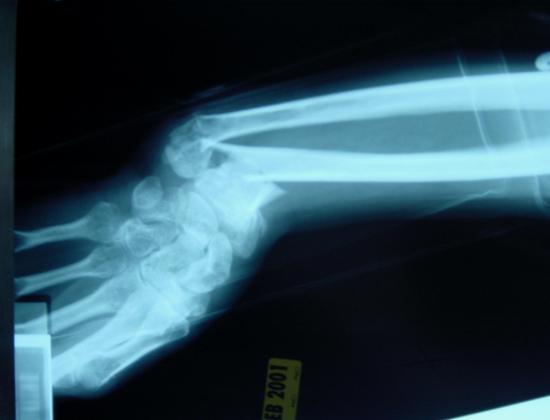

Ako ste ikada slomili neku kost u tijelu, znate kako ide procedura: prvo vas jako boli, pa vam se kost namjesti (što vas također jako boli), pa vam se stavi gips koji onda držite koliko god, dok vas paralelno sve svrbi i smeta.